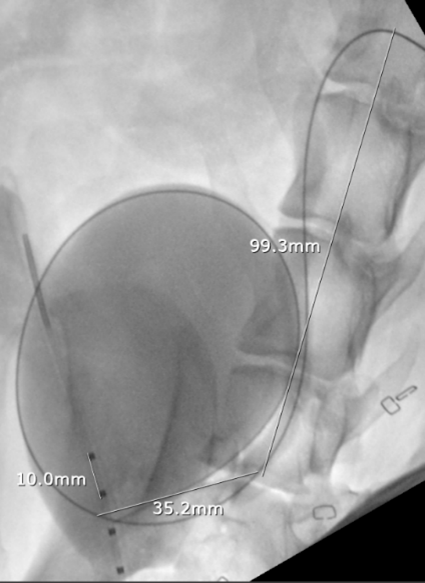

A 3.7 Fr fenestrated ureteral stent was positioned percutaneously from the renal pelvis to the bladder, successfully bypassing the tumor-associated obstruction without surgical incisions.

No intraoperative or postoperative complications occurred. Postoperative imaging confirmed ideal stent placement, and the patient demonstrated appropriate urine output.